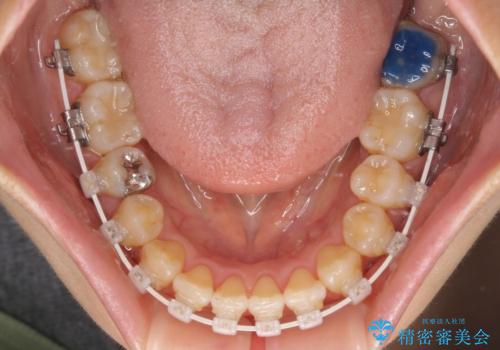

- 矯正装置

- 審美装置

マウスピース矯正は自己管理が煩わしいとのことで、ワイヤー装置による矯正治療を行うこととしました。